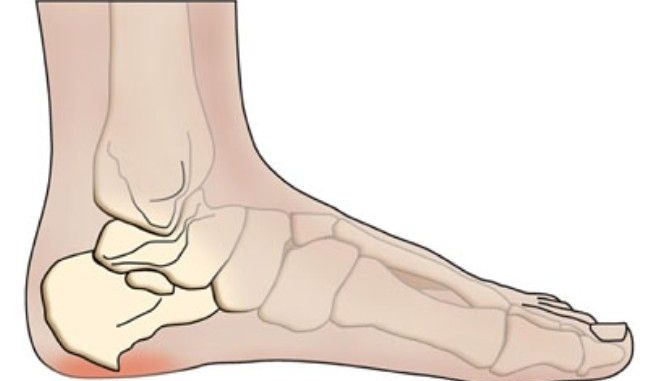

La spina calcaneare è particolarmente fastidiosa e dolorosa; si tratta di una vera e propria malattia, che colpisce il piede, in particolare il tallone. In questo caso, si verifica una degenerazione della fascite plantare, cioè un’infiammazione che peggiora progressivamente, causando con il tempo la comparsa di una sporgenza anomala in prossimità del tallone, una neoformazione ossea all’origine del dolore e dei fastidi.

Il sintomo più importante della spina calcaneare è sicuramente il dolore trafittivo e pungente nella zona del tallone. In questi casi, infatti, quando il piede va in appoggio su una superficie, il dolore tende ad acuirsi ulteriormente. Comunque, prima di diagnosticare questa patologia, occorre accertarsi che il fastidio non dipenda da altre cause.